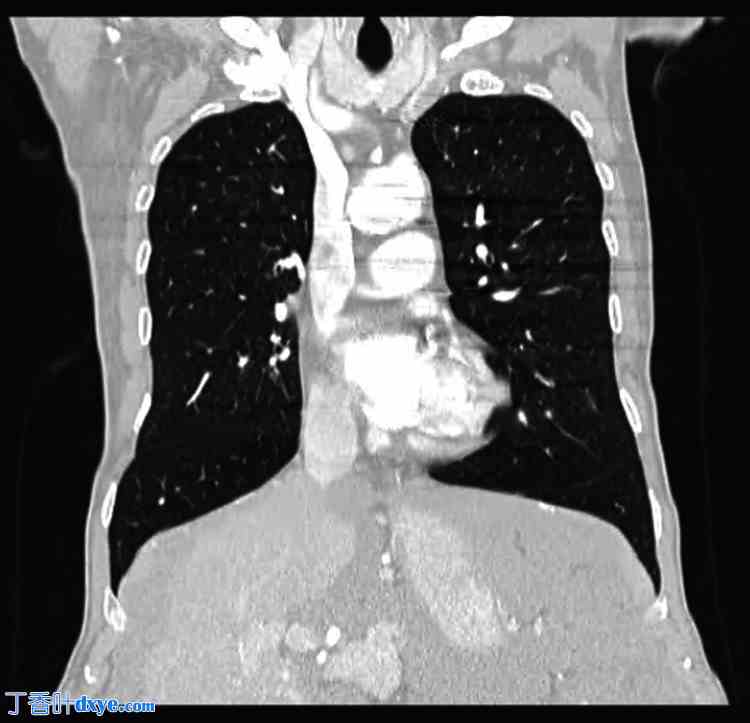

患者的HIV、干扰素-γ释放试验和肝炎检测结果均为阴性。梅毒螺旋体检测(滴度稀释度1:1280)阳性提示为未经治疗的晚期梅毒,因此开始使用青霉素治疗。同时,进一步的诊断性检查包括胸部CT扫描(图3)、上消化道内镜检查(图4)和结肠镜检查(图5),均未发现梗阻和肿瘤的迹象。腹部MRI检查显示腹膜癌病征,提示肠道肿瘤,但无法确定其来源。

图3. 胸部CT扫描(冠状面)。未观察到可疑病变。